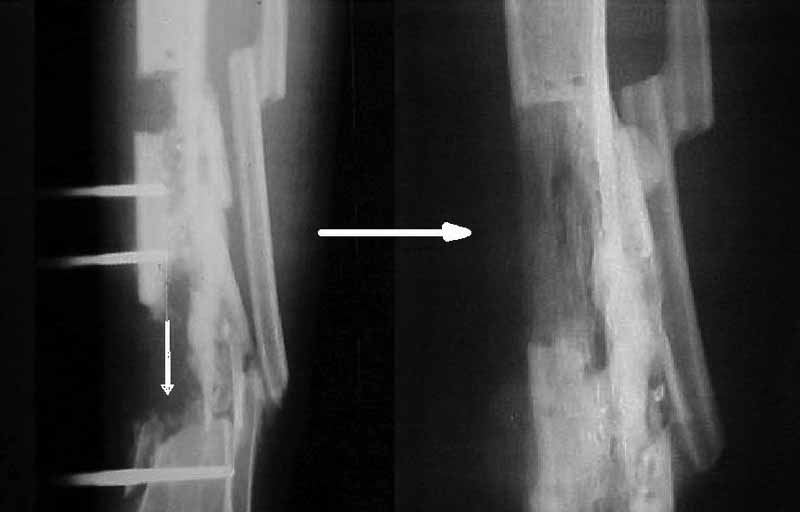

Я бы сделал пластику мягких тканей (торакодорзальный лоскут совместно с микрохирургами или пластику латеральной головкой икроножной мышцы) и выполнил бы краевой отщеп большеберцовой кости для его дистракции аппаратом в проксимальном направлении (рис. 1 – пример применения отщепа (авторство не мое), рис. 2 – схема предлагаемого варианта замещения дефекта кости).

Малоберцовую кость я бы пока не трогал. Она сослужит хорошую службу при начале нагрузки на ногу - будет служить дополнительным стабилизирующим и элементом.